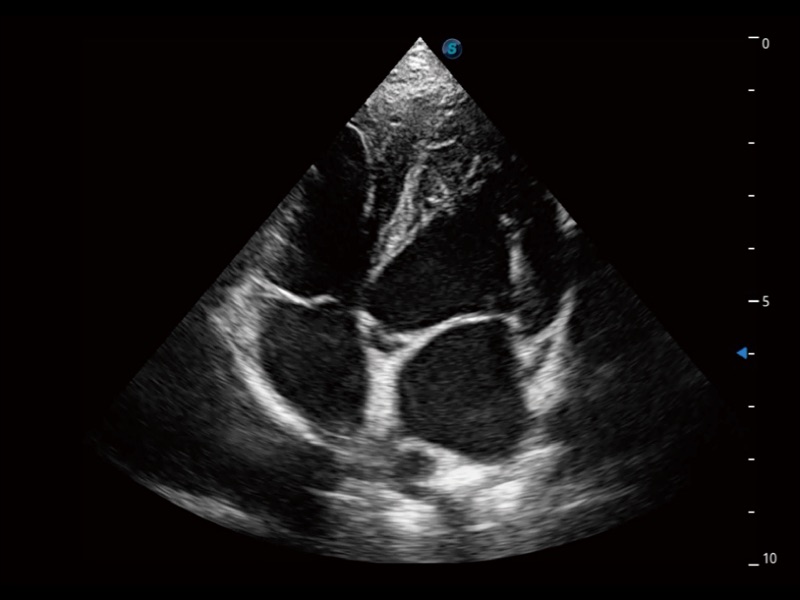

能夠基于左心室壁追蹤和辛普森法,自動計(jì)算射血分?jǐn)?shù),支持多個可移動點(diǎn)描跡,與手動測量相比,極大節(jié)省了動物醫(yī)生的時(shí)間和精力。